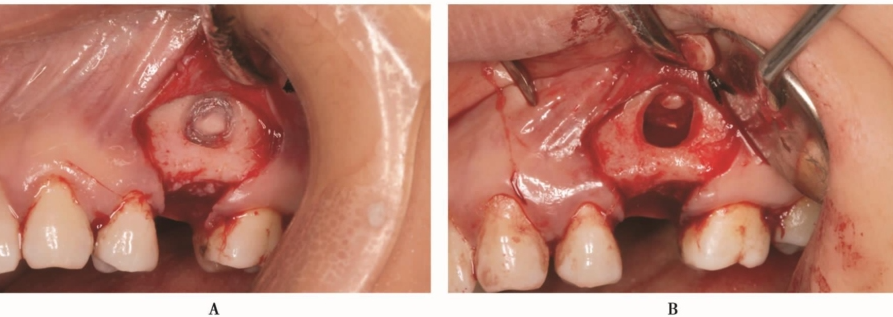

超声骨刀侧壁开窗,剥离上颌窦黏膜(图13A)。但在剥离的过程中,由于开窗中央骨块锐利的边缘,侧壁上颌窦黏膜发生穿孔(图13B)。采用胶原膜封闭穿孔后,植入Bioss®骨粉,采用延期种植。

图13 侧壁开窗A.超声骨刀开窗;B.分离窦黏膜,但出现小的穿孔